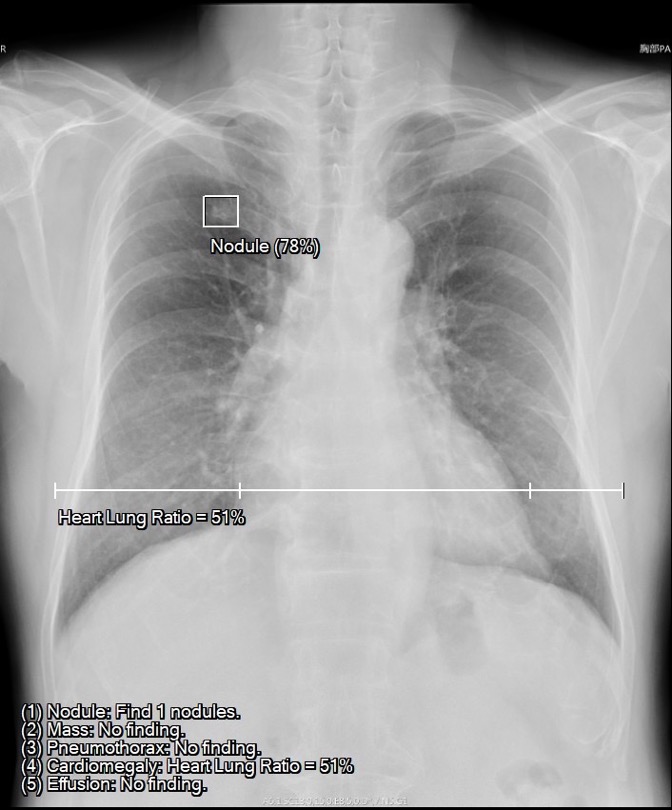

經(jīng)過AIIE推理計算后,整合后的PACS系統(tǒng)會通過病例列表顯示出病癥的嚴(yán)重程度,比如氣胸、大面積胸腔積液會在系統(tǒng)中被標(biāo)注為危急,而中小型氣胸、結(jié)節(jié)腫塊、心臟肥大、主動脈弓鈣化等其它陽性病癥就被標(biāo)注為優(yōu)先狀態(tài),這樣醫(yī)師可以第一時間處理最需要醫(yī)療救助的危重病患。這一功能,無論是在醫(yī)師日常診斷,還是遠(yuǎn)程會診探討說明病情等場景都會起到很好的輔助作用。

1. 結(jié)節(jié)自動檢測與定位。

2. 心臟肥大自動偵測??烧{(diào)整閾值:預(yù)設(shè)心肺比大于XX%,即進(jìn)行異常提示